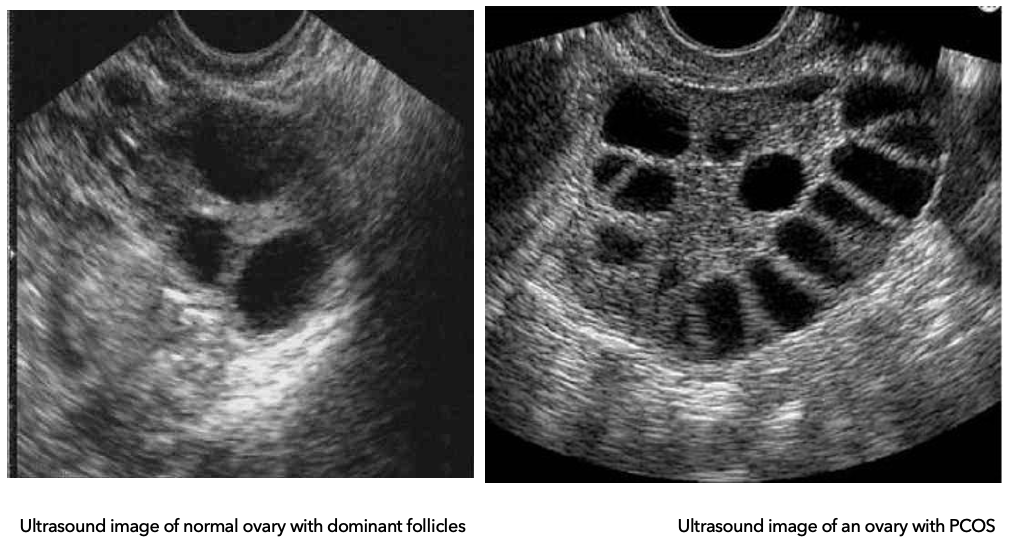

What is the difference between a normal ovary and a PCOS ovary on ultrasound?

Diagnostics: Ovarian Types

Normal ovary:

Multiple follicles develop

One becomes dominant → ovulation (egg released)

Others regress and are reabsorbed

PCOS ovary:

Follicles begin to grow but get arrested (don’t fully mature)

No dominant follicle → no ovulation

Follicles do not regress → accumulate in ovary

Polycystic ovaries on ultrasound

Appear as “string of pearls” pattern